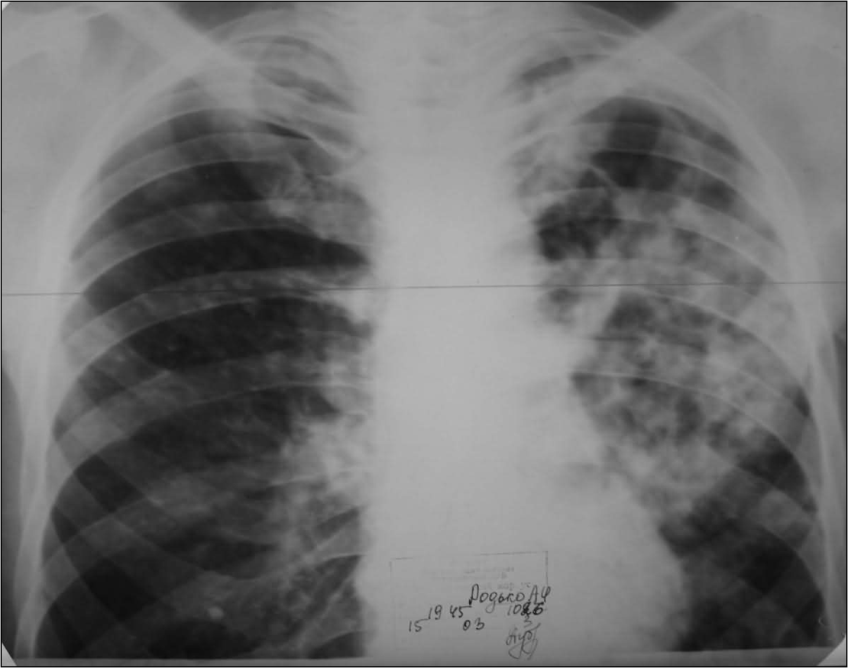

Иллюстрации по теме очагового и инфильтративного туберкулеза

Раздел: Фотодневник открытий